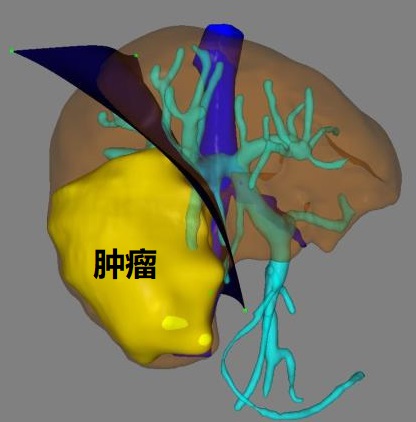

一、术前利用计算机3D模拟可视化技术测算肿瘤的体积和形态、癌栓的位置、血管的走行以及切除肿瘤后剩余肝脏的体积,制定了首选手术方案及备选手术方案;

经过周密的术前准备,2018年10月17日,肝胆外科李晓武教授团队给患者实施了精准右半肝切除术。术中探查结果与术前规划基本一致,整个手术历时2.5小时,术中釆用凝血器切肝,半肝血流阻断,切肝时间18分钟,切肝过程“0”出血,“0”输血,整个手术过程出血100ml。标本大小13*10cm,完美展现了精准肝切除、无血肝切除的理念。术后,患者生命体征平稳,清醒后送回普通病房。